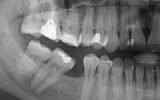

The

patient had his bottom six removed years ago. The teeth had become misaligned

and orthodontic therapy was used to correct the bite of the entire dentition.

After 6 months of successful

orthodontic treatment, we were finally able to place the implant and the

provisional crown. After 4 months of ingrowth, aligners were removed and a full

ceramic crown was placed. The treatment was successfully completed!✋🏽😉